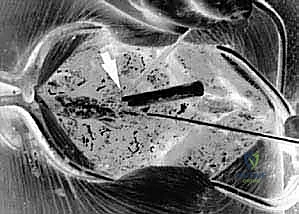

المرحلة الرابعة: وضع البراغي وأدوات التثبيت (Instrumentation)

هذه هي الخطوة الأكثر دقة. اعتمادًا على حالة المريض، يقوم الدكتور هطيف بإحدى العمليتين:

- دمج C1-C2 (C1-C2 Fusion): يتم إدخال براغي دقيقة جدًا في الكتل الجانبية للفقرة الأولى (C1 Lateral Mass Screws)، وبراغي أخرى في عنيق الفقرة الثانية (C2 Pedicle/Pars Screws). يتم بعد ذلك توصيل هذه البراغي بقضبان معدنية صغيرة لتثبيت المفصل تمامًا.

- دمج الجمجمة بالفقرات (Occipitocervical Fusion): إذا كانت المشكلة تشمل الجمجمة، يتم تثبيت صفيحة معدنية (Plate) في العظم القذالي للجمجمة باستخدام براغي خاصة، ثم يتم توصيل هذه الصفيحة بقضبان معدنية تمتد إلى البراغي المزروعة في الفقرات العنقية (C2, C3، أو أسفل من ذلك حسب الحاجة).